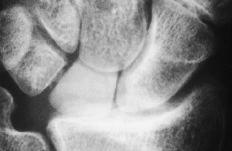

Figura 1. Artroplastia de silicona en semilunar.

Figura 4. Radiografía posteroanterior de muñeca donde se muestra una luxación cubital del implante junto con un colapso carpiano y una traslación cubital.

La relación de la altura carpiana presentó postoperatoriamente un valor medio de 0,47 (mínimo: 0,40 y máximo: 0,53). Por tanto, la intervención no es capaz de frenar la evolución a un colapso carpiano. El valor medio postoperatorio de la relación de la distancia cubitocarpiana es de 0,26 (mínimo: 0,23 y máximo: 0,32). Por tanto, la intervención no es capaz de frenar la traslación cubital que se da en fases avanzadas de la enfermedad (Tabla 2).